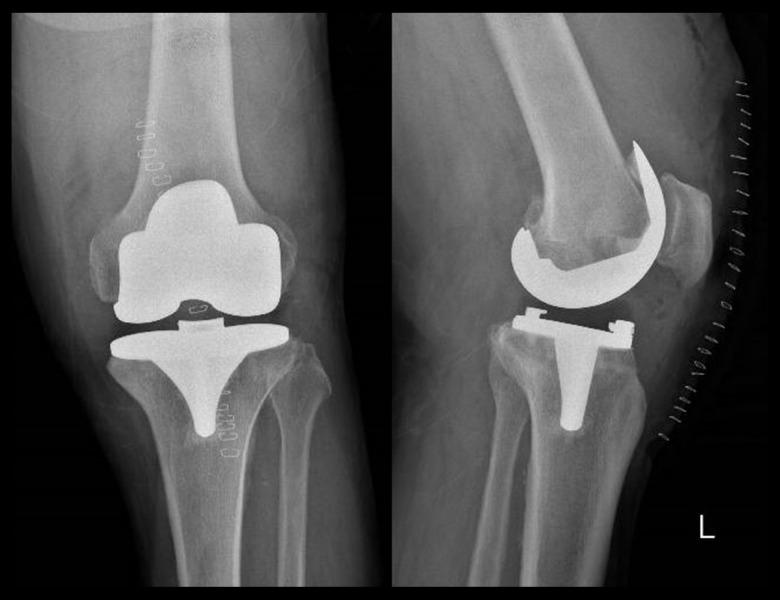

BACKGROUND Total knee arthroplasty (TKA) is frequently used in the treatment of end-stage gonarthrosis, and the patient satisfaction rate varies. This study aimed to reveal the change in mid-term patient satisfaction results and functional scores of patients with low early postoperative satisfaction scores. MATERIAL AND METHODS We included 163 patients who underwent total knee prosthesis between September 2017 and February 2018. Among these patients, early (6 months) and mid-term (24 months) satisfaction and functional results of 34 patients with low satisfaction scores (Likert evaluations 1, 2, and 3) were evaluated. We assessed early-term functional results and satisfaction rates, mid-term analysis of patients who were not satisfied in the early period, and the relationship between functional scores and satisfaction. RESULTS The Likert score was 4 or 5 in 124 (80%) of 158 patients, and early dissatisfaction was detected in 34 patients (20%). In the early-period dissatisfied group, satisfaction scores 6 months after surgery were 1.9±1.1 (1-3) and 4.2±1 (3-5) 24 months after surgery. A statistically significant difference was observed between the dissatisfied group's early and mid-term KSS and KS values. A correlation was observed between satisfaction scores and KS and KSS scores (P<0.05). CONCLUSIONS Patients who do not have mechanical problems with total knee arthroplasty but are not satisfied with the surgery in the early period can be satisfied over time after regular follow-up, appropriate communication and information, and effective rehabilitation.

我们纳入了 2017 年 9 月至 2018 年 2 月期间接受全膝关节假体置换术的 163 例患者。其中,34 例早期满意度评分较低(Likert 评分为 1、2、3)患者的早期(6 个月)和中期(24 个月)满意度和功能结果进行了评估。我们评估了早期的功能结果和满意度,以及早期不满意患者的中期分析,以及功能评分与满意度之间的关系。

158 例患者中有 124 例(80%)的 Likert 评分为 4 或 5,有 34 例(20%)患者在早期出现不满意。在早期不满意组中,术后 6 个月的满意度评分为 1.9±1.1(1-3),术后 24 个月为 4.2±1(3-5)。不满意组的 KSS 和 KS 值在早期和中期均存在显著差异。满意度评分与 KS 和 KSS 评分之间存在相关性(P<0.05)。